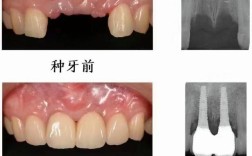

- 资质与经验: 优先选择硕士及以上学历(正畸是高度专业化的领域)、有公立医院工作背景(尤其是知名三甲医院)的医生,查看医生的从业年限、处理过的病例数量和复杂程度,要求看与你情况类似的案例(治疗前、中、后对比图)。